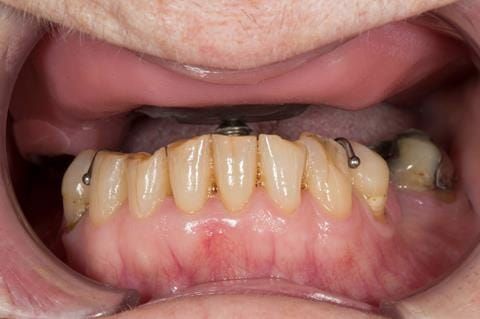

- Cobalt chromium reinforced gasket denture - using a Molloplast B "O" ring to retain and stabilise the denture. This was my professional preference as this was the least invasive and simplest solution to this dental problem. Should the UR7 require removal in the future - an artificial tooth could be added - resulting in a complete denture. The patient would have adapted to the denture fully by this stage and have good neuromuscular control of the prosthesis.

Following consultation and second discussion appointment the patient chose to have option 2 namely, a window denture - maxillary cobalt chromium based partial denture. The clinical situation and treatment process is shown in detail below with photographs. The patient was successfully rehabilitated with this and her quality of life considerably improved. The clinical work was provided by Finlay and the technical work by Rowan.